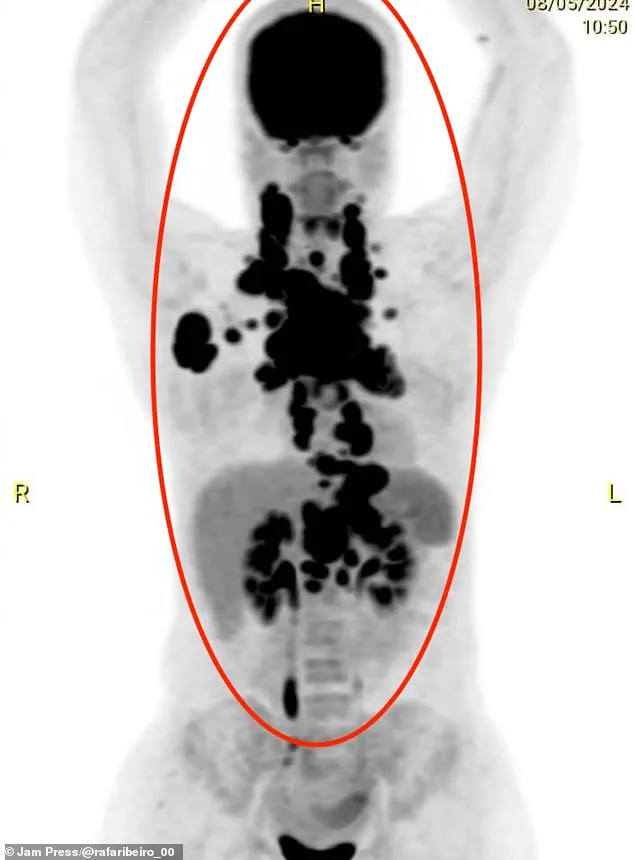

It wasn’t until she collapsed and was unable to eat that scans revealed the full extent of the damage: her upper body was riddled with tumors, and her internal organs were under severe duress. "They told my husband I could die within 24 hours," she said. "Miraculously, I survived." The turning point came when she contracted a deadly hospital superbug during chemotherapy, leading to a nine-day induced coma. "This period of fasting helped me achieve remission," she explained. "If I hadn’t caught this infection and ended up in a coma, they might not have been able to control the disease." The superbug, a common but often fatal complication of hospital stays, forced doctors to put Rafaela into a medically induced coma to stabilize her condition.